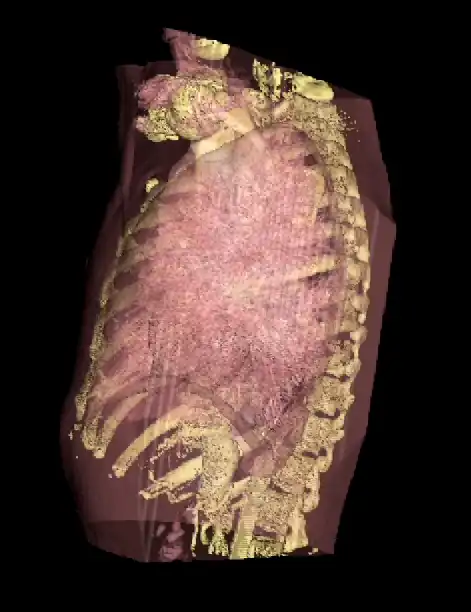

An opacity table can be applied to the results so that surfaces from internal features can also be visualized. As an example, two surfaces have been identified in the following image from the CT scan where voxel values from bone surfaces are coded in an opaque yellow colour and tissue surfaces in a transparent shade of red.

A second example of using an opacity table is shown in the following figure. Here, axial CT data from the patient's airways have been segmented using a region growth technique and the result processed using surface rendering, with full opacity as shown in the left panel and with a reduced opacity (30%) as shown in the right panel: